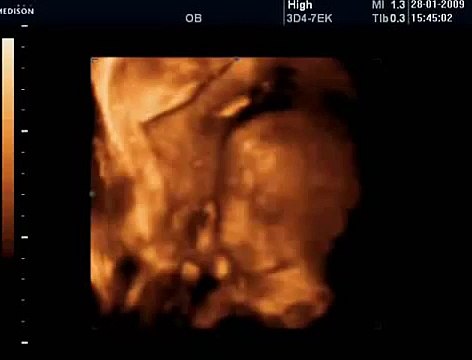

33 Haftalık Gebelik Bebek Ultrason Görüntüsü

Hafta hafta gebelik dönemi 33 haftalık bebek ultrason görüntüsü. Gebelikte 33. hafta daha çok bilgi için gebelikveannelik.com/33-hafta-gebelik sayfamızı ziyaret edebilirsiniz.